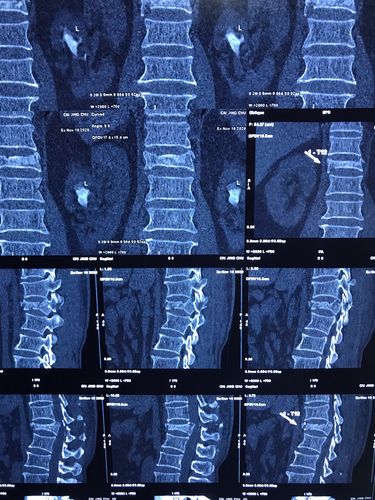

ct示:t12椎体压缩性粉碎性骨折并骨性椎管狭窄严重.

t12椎体压缩性骨折(田欢)